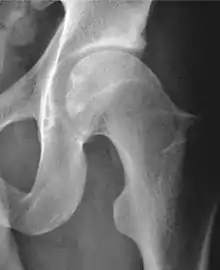

Radiograph of a cam type impingement.

Projectional radiography ("X-ray")is often considered first line for FAI.[10] Anterior-posterior pelvis and a lateral image of the hip in question should be attained.[10] A 45-degree Dunn view is also recommended.[10][19]